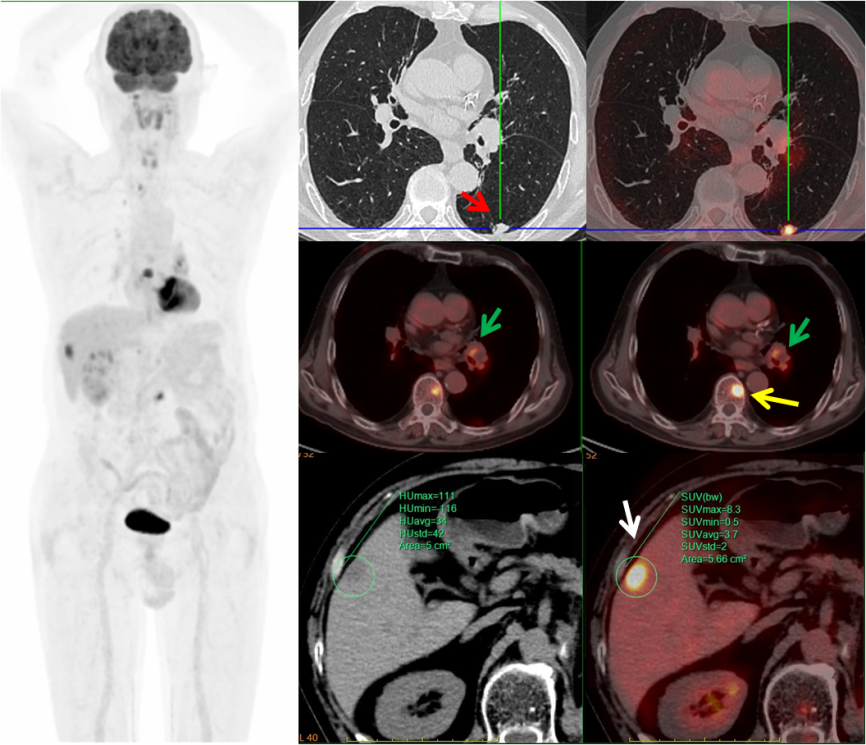

图片

病例1,PET/CT示右肺下叶、贲门代谢异常,符合双原发癌;之后患者行CT引导下肺部病变穿刺,病理证实原发肺腺癌,行胃镜下贲门病变活检,病理证实原发贲门腺癌。

病例3,中年男性,左肾癌术后三个月,PET/CT示左肺下叶(红箭)、左肺门淋巴结(绿箭)、肝脏(白箭)、多发椎体(黄箭)高代谢灶,考虑左肺下叶原发MT可能,病理证实为小细胞神经内分泌癌。